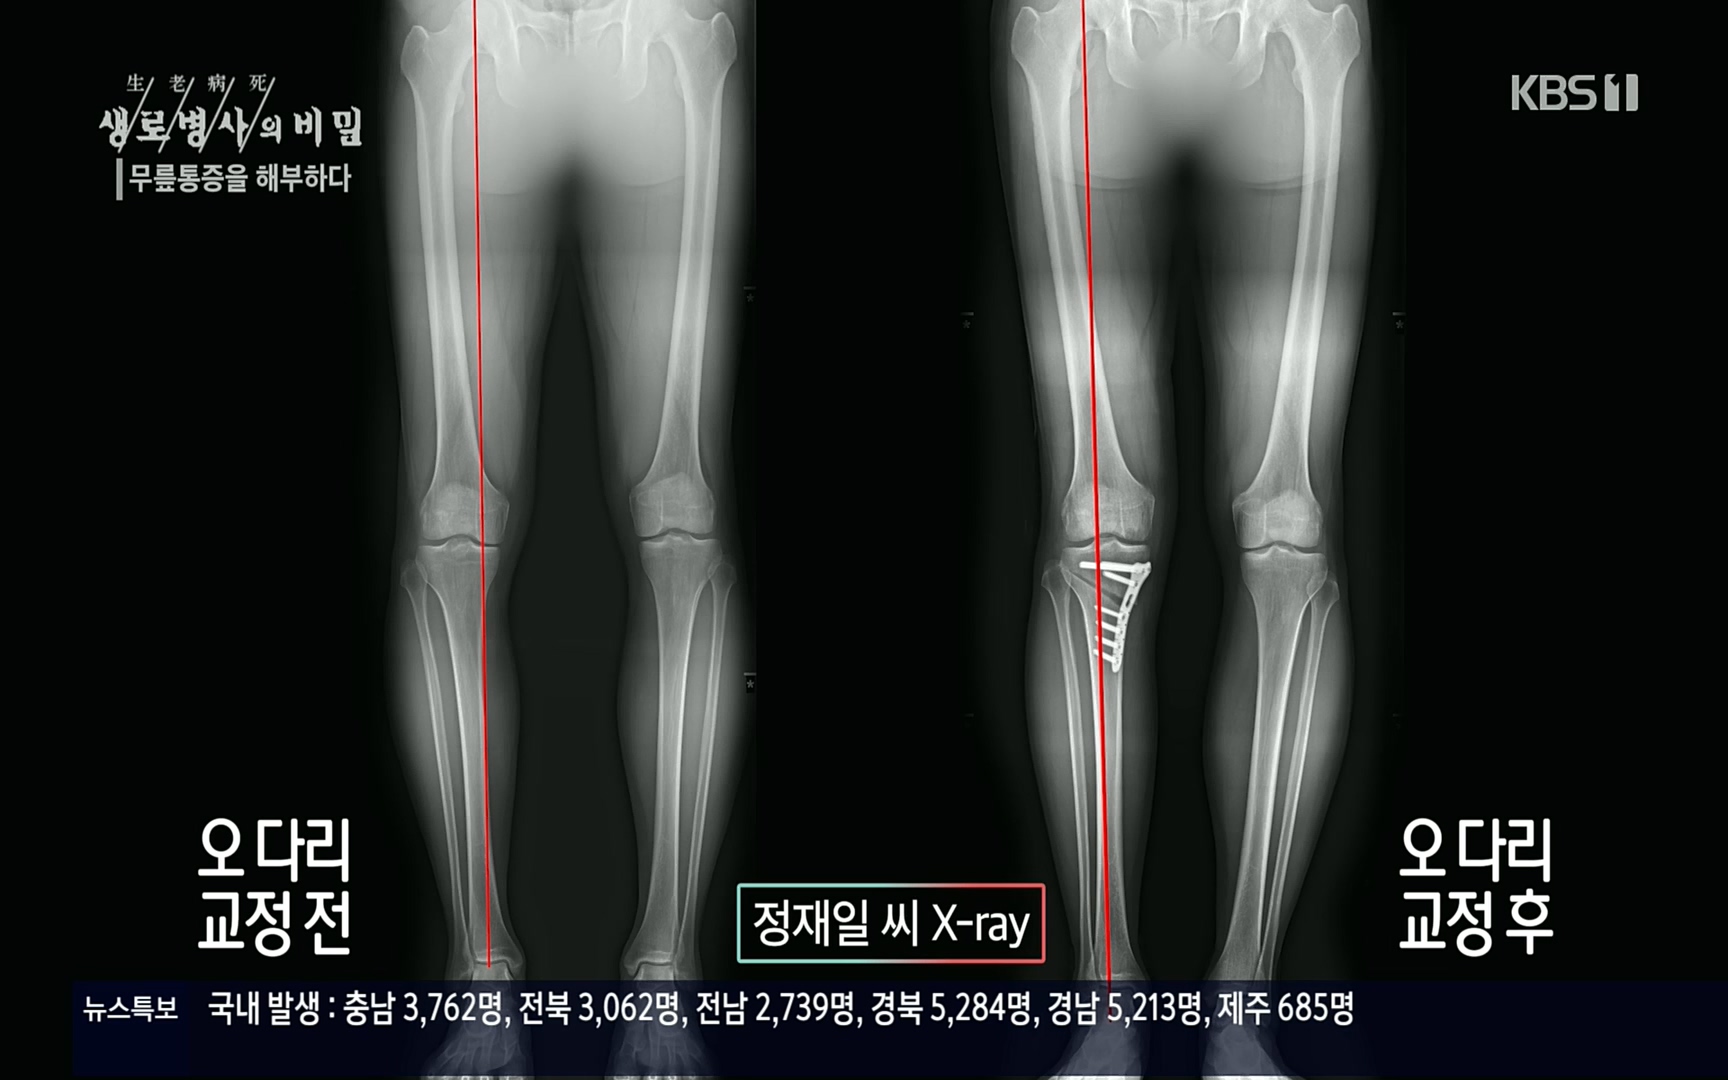

무릎통증을 해부하다

안쪽에 있는 반월상연골판 쪽에 아무래도 하중이 많이 실리게 되겠죠